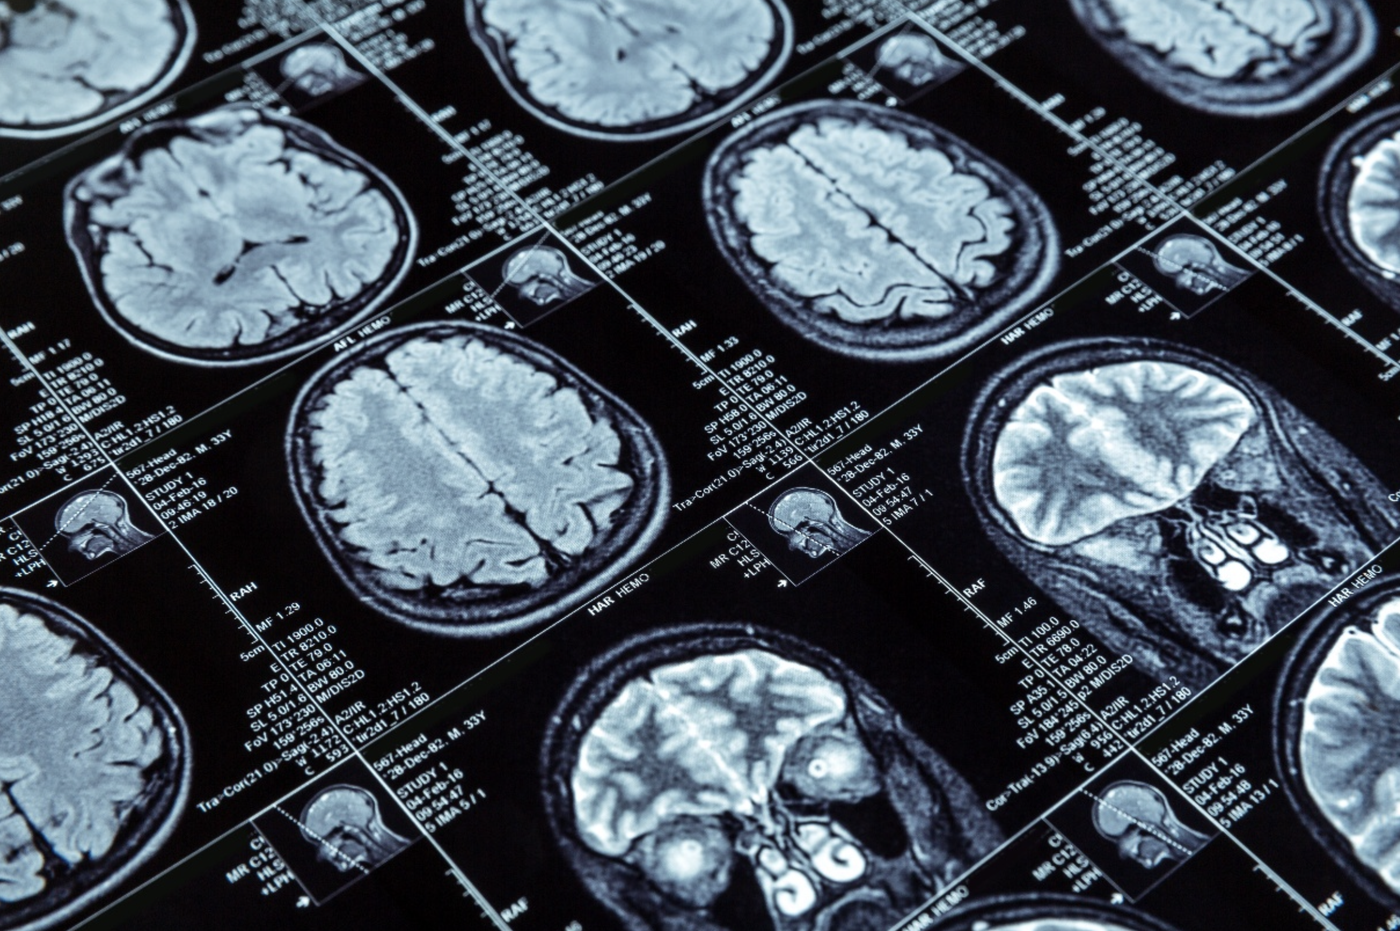

Si chiama Tenecteplase è il nuovo farmaco trombolitico per l'ictus, è più rapido da somministrare, più efficace nelle occlusioni delle grandi arterie e, in casi selezionati, può essere utilizzato fino a 24 ore dall’esordio dei sintomi.

"Le nuove linee guida americane, pubblicate il 26 gennaio, sottolineano l’importanza di questa molecola - spiega Del Sette - mettono in evidenza il ruolo di questo nuovo farmaco, che ha un nome un po’ difficile, Tenecteplase, ma che sostanzialmente funziona come il precedente: serve a sciogliere il trombo che si forma nel cuore o nelle arterie e che chiude completamente la circolazione, causando l’ischemia cerebrale".

Non solo rapidità. "Il Tenecteplase si è dimostrato più efficace soprattutto quando l’occlusione riguarda arterie di grosse dimensioni, come quelle del collo o i principali rami cerebrali - sottolinea - nelle prime ore, entro le quattro ore e mezza, è più efficace del precedente e può essere utilizzato al suo posto con un intervento più rapido".

La finestra temporale resta un punto cruciale. La regola aurea non cambia: intervenire il prima possibile. "Il vecchio adagio ‘il tempo è cervello’ vale sempre. Questo non significa che ce la si possa prendere comoda - precisa il direttore della Neurologia - tuttavia, grazie a diagnosi molto accurate e a TAC specifiche, in pazienti selezionati il farmaco può essere impiegato fino a 24 ore dall’esordio dei sintomi. È un’opzione in più per quei casi che arrivano in ospedale dopo nove, dieci ore o anche più tardi, ma il nostro auspicio è di non doverlo mai usare in tempi così tardivi. I pazienti devono arrivare sempre prima".

L’ictus resta una delle principali cause di morte e disabilità. Nel mondo si registrano circa 12 milioni di nuovi casi ogni anno. In Italia i casi superano i 90 mila all’anno, mentre in Liguria si stimano tra i 2 mila e i 2.500 episodi annuali. È la seconda causa di morte a livello globale e la prima causa di disabilità nell’adulto. Numeri che rendono evidente quanto ogni minuto, e ogni nuovo strumento terapeutico, possano fare la differenza.